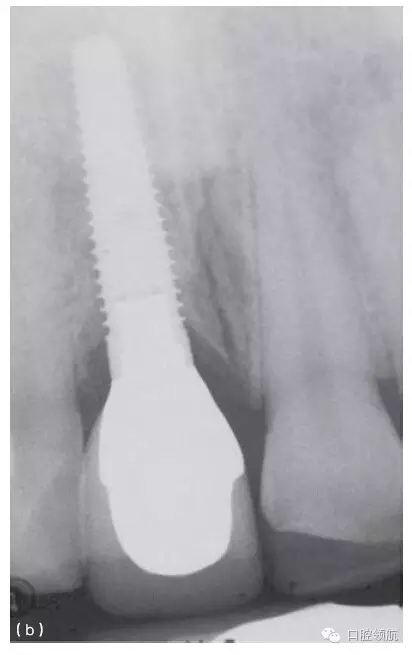

其他的美學(xué)問題與種植體植入位置不當(dāng)(圖10.20a,b),以及植入前存在骨吸收有關(guān)。骨吸收的存在使種植體無法植入到理想位置,造成單冠之間或是固定局部義齒的橋體之間存在頸部間隙(圖10.21)。

圖10.20 (a)中切牙種植體的位置太偏唇側(cè),采用定制的基臺盡可能補償頰側(cè)的錯位。(b)一并更換相鄰的兩個冠修復(fù)體以獲得更滿意的結(jié)果。

種植體植入太偏唇側(cè),將造成明顯的美學(xué)問題,而且通常很難克服(圖10.20a,b)。